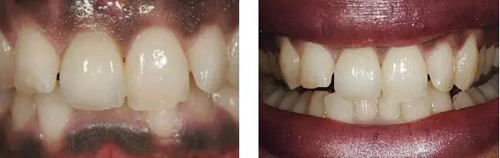

圖10、剛植入種植體當(dāng)天的情況(左)和植入種植體1年時(shí)的情況(右)。

圖11、牙冠戴入1個(gè)月以后。軟組織外形良好,形成了良好的弧線形牙齦形態(tài)而沒(méi)有瘢痕。保持了原有的色素沉著的顏色和形狀。

圖12、種植術(shù)后1年顯示良好的美學(xué)效果。